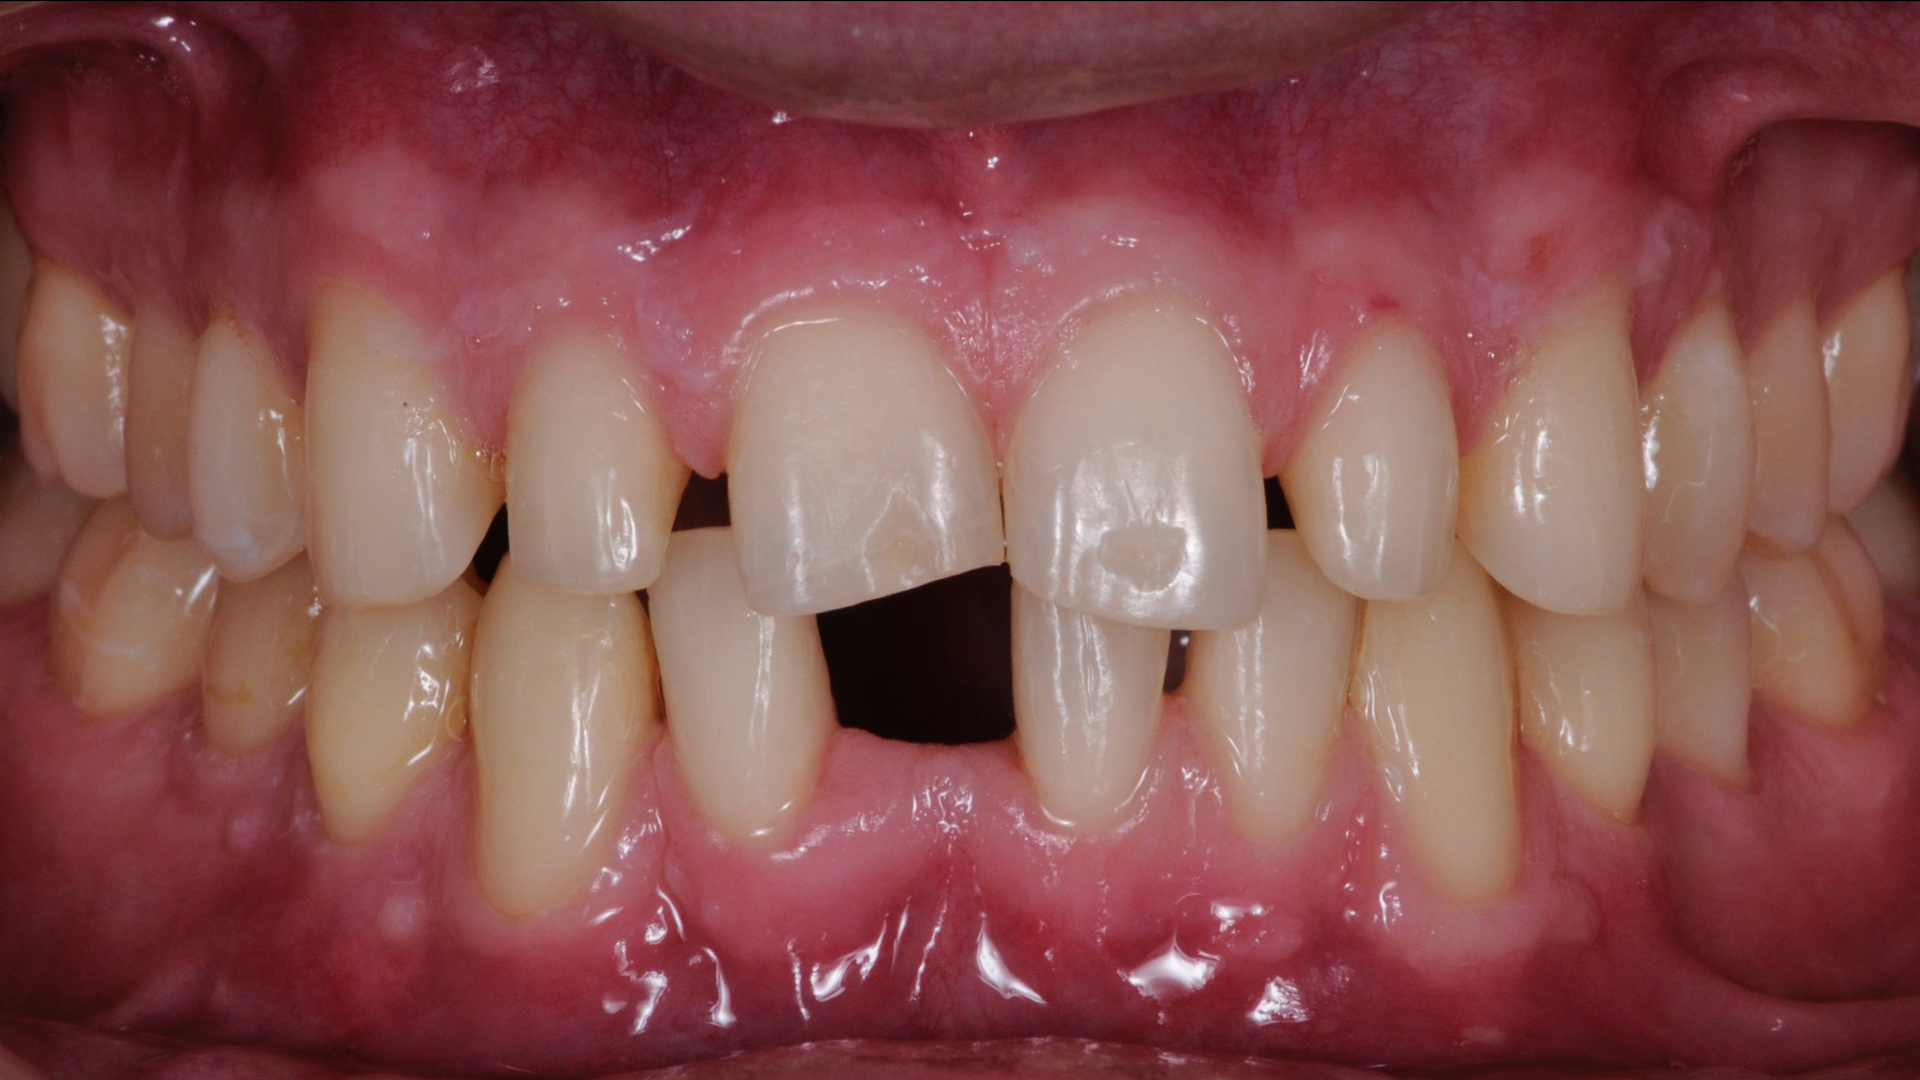

Zâmbetul său, aşa cum se poate vedea în fotografii, nu îndeplinea toate cerințele pe care el le avea punct de vedere estetic, dar nici funcţional (adică modul în care dinţii muşcă şi conlucrează) situaţia nu era foarte ideală. Această situaţie a fost rezultatul unei loterii genetice, dar şi a unui tratament ortodontic nereușit.

În situaţia de faţă, condiţiile au fost foarte bune pentru un tratament complet, minim-invaziv. S-au putut pune faţete dentare fără a șlefui dinții. Acest fapt s-a datorat în mare dimensiunilor dinţilor, dar şi spaţiilor existente între aceştia.